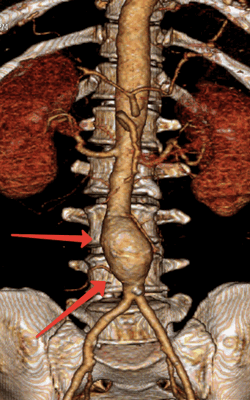

- аорты - для исключения аневризмы и расслоения (диссекции) стенки

Как выглядит аневризма аорты на КТ. Аневризма аорты - расширение основного артериального сосуда. Она может быть как в грудном отделе аорты, так и в брюшном, так и в обоих сразу. Сегодня при подозрении на аневризму аорты КТ выполняется обязательно. Исследование выявляет размеры и форму аневризмы, а также позволяет исключить опасное осложнение - расслоение стенки аорты!